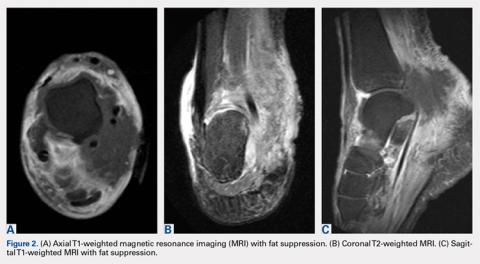

MRI of the foot and ankle was reviewed and demonstrated a large soft-tissue mass over the medial aspect of the ankle extending posteriorly to engulf the medial flexor tendons and medial neurovascular bundle (Figures 2A-2C). Interestingly, the radiologist’s report only mentioned a “large region of devitalized tissue underlying the known medial ankle ulcer which extended to the tibiotalar and subtalar joints and bone marrow changes in the talus most compatible with osteomyelitis.” FDG PET-CT images from the patient’s past 2 years were reviewed, and the radiologist was contacted to confirm the negative findings. Unfortunately, FDG PET-CT performs no routine imaging below the elbow or knee when evaluating for this particular malignancy (Figure 3).At presentation, our differential diagnosis included recurrence of the malignancy, secondary malignancy, infection, and inflammatory disease. After a lengthy discussion with the patient and consultation with our institution’s musculoskeletal oncologist, the decision was made to perform a right-ankle mass biopsy and marginal excision with wound irrigation and débridement and tarsal tunnel release.